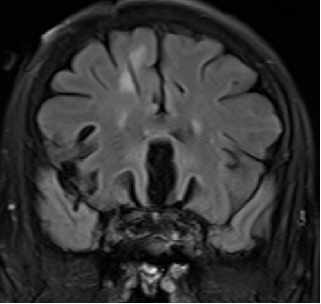

2015-4-1 MRI

诊断

脑膜癌?

特发性肥厚性硬脊膜炎?

进展性特发性肥厚性硬脊膜炎